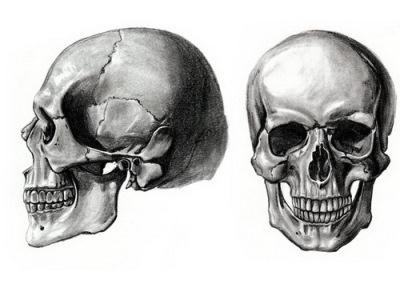

koponya-

A koponya egy felnőtt formában 23 fő csontok, 3 gödrök részeként hallási mozgás és 32 fogak. A koponya van osztva neyrokranium (agy) és az arc (zsigeri).

A szerkezet a koponyacsontok

A koponyacsontok képződött lapos, tagjai kompakt anyag, és egy szivacs (diploe). Részéről az agy lemez egy ilyen anyag nagyon törékeny, és könnyen törik a sérülések. A csonthártya csatlakozik a csontok az ízületek, a alkotó más részein a subperiosteal tér van, amelynek egy laza szerkezetű. Belülről a kemény héj működik az agy.

Típusai koponya kapcsolatok

A fő típusú csont ízületi neyrokraniuma - egy syndesmosis. A legtöbb ilyen fúziók képviseli csipkézett varratok; csak közötti időbeli és parietális csontjait halad pehely varrat. Arc koponya lapos hegek. Anatómiailag a varrat gyakran nevezik a nevét segítségével csatlakoznak a csontjai alkotják a koponya. Vegyület koponya csont tartalmaz egy sagittalis varrat (gőz alkalmazásával összeköti a falcsont a koponya), koronális (frontális és parietális összeköti csontok) és lambdoid (összekötő occipitalis és parietális csontjait).